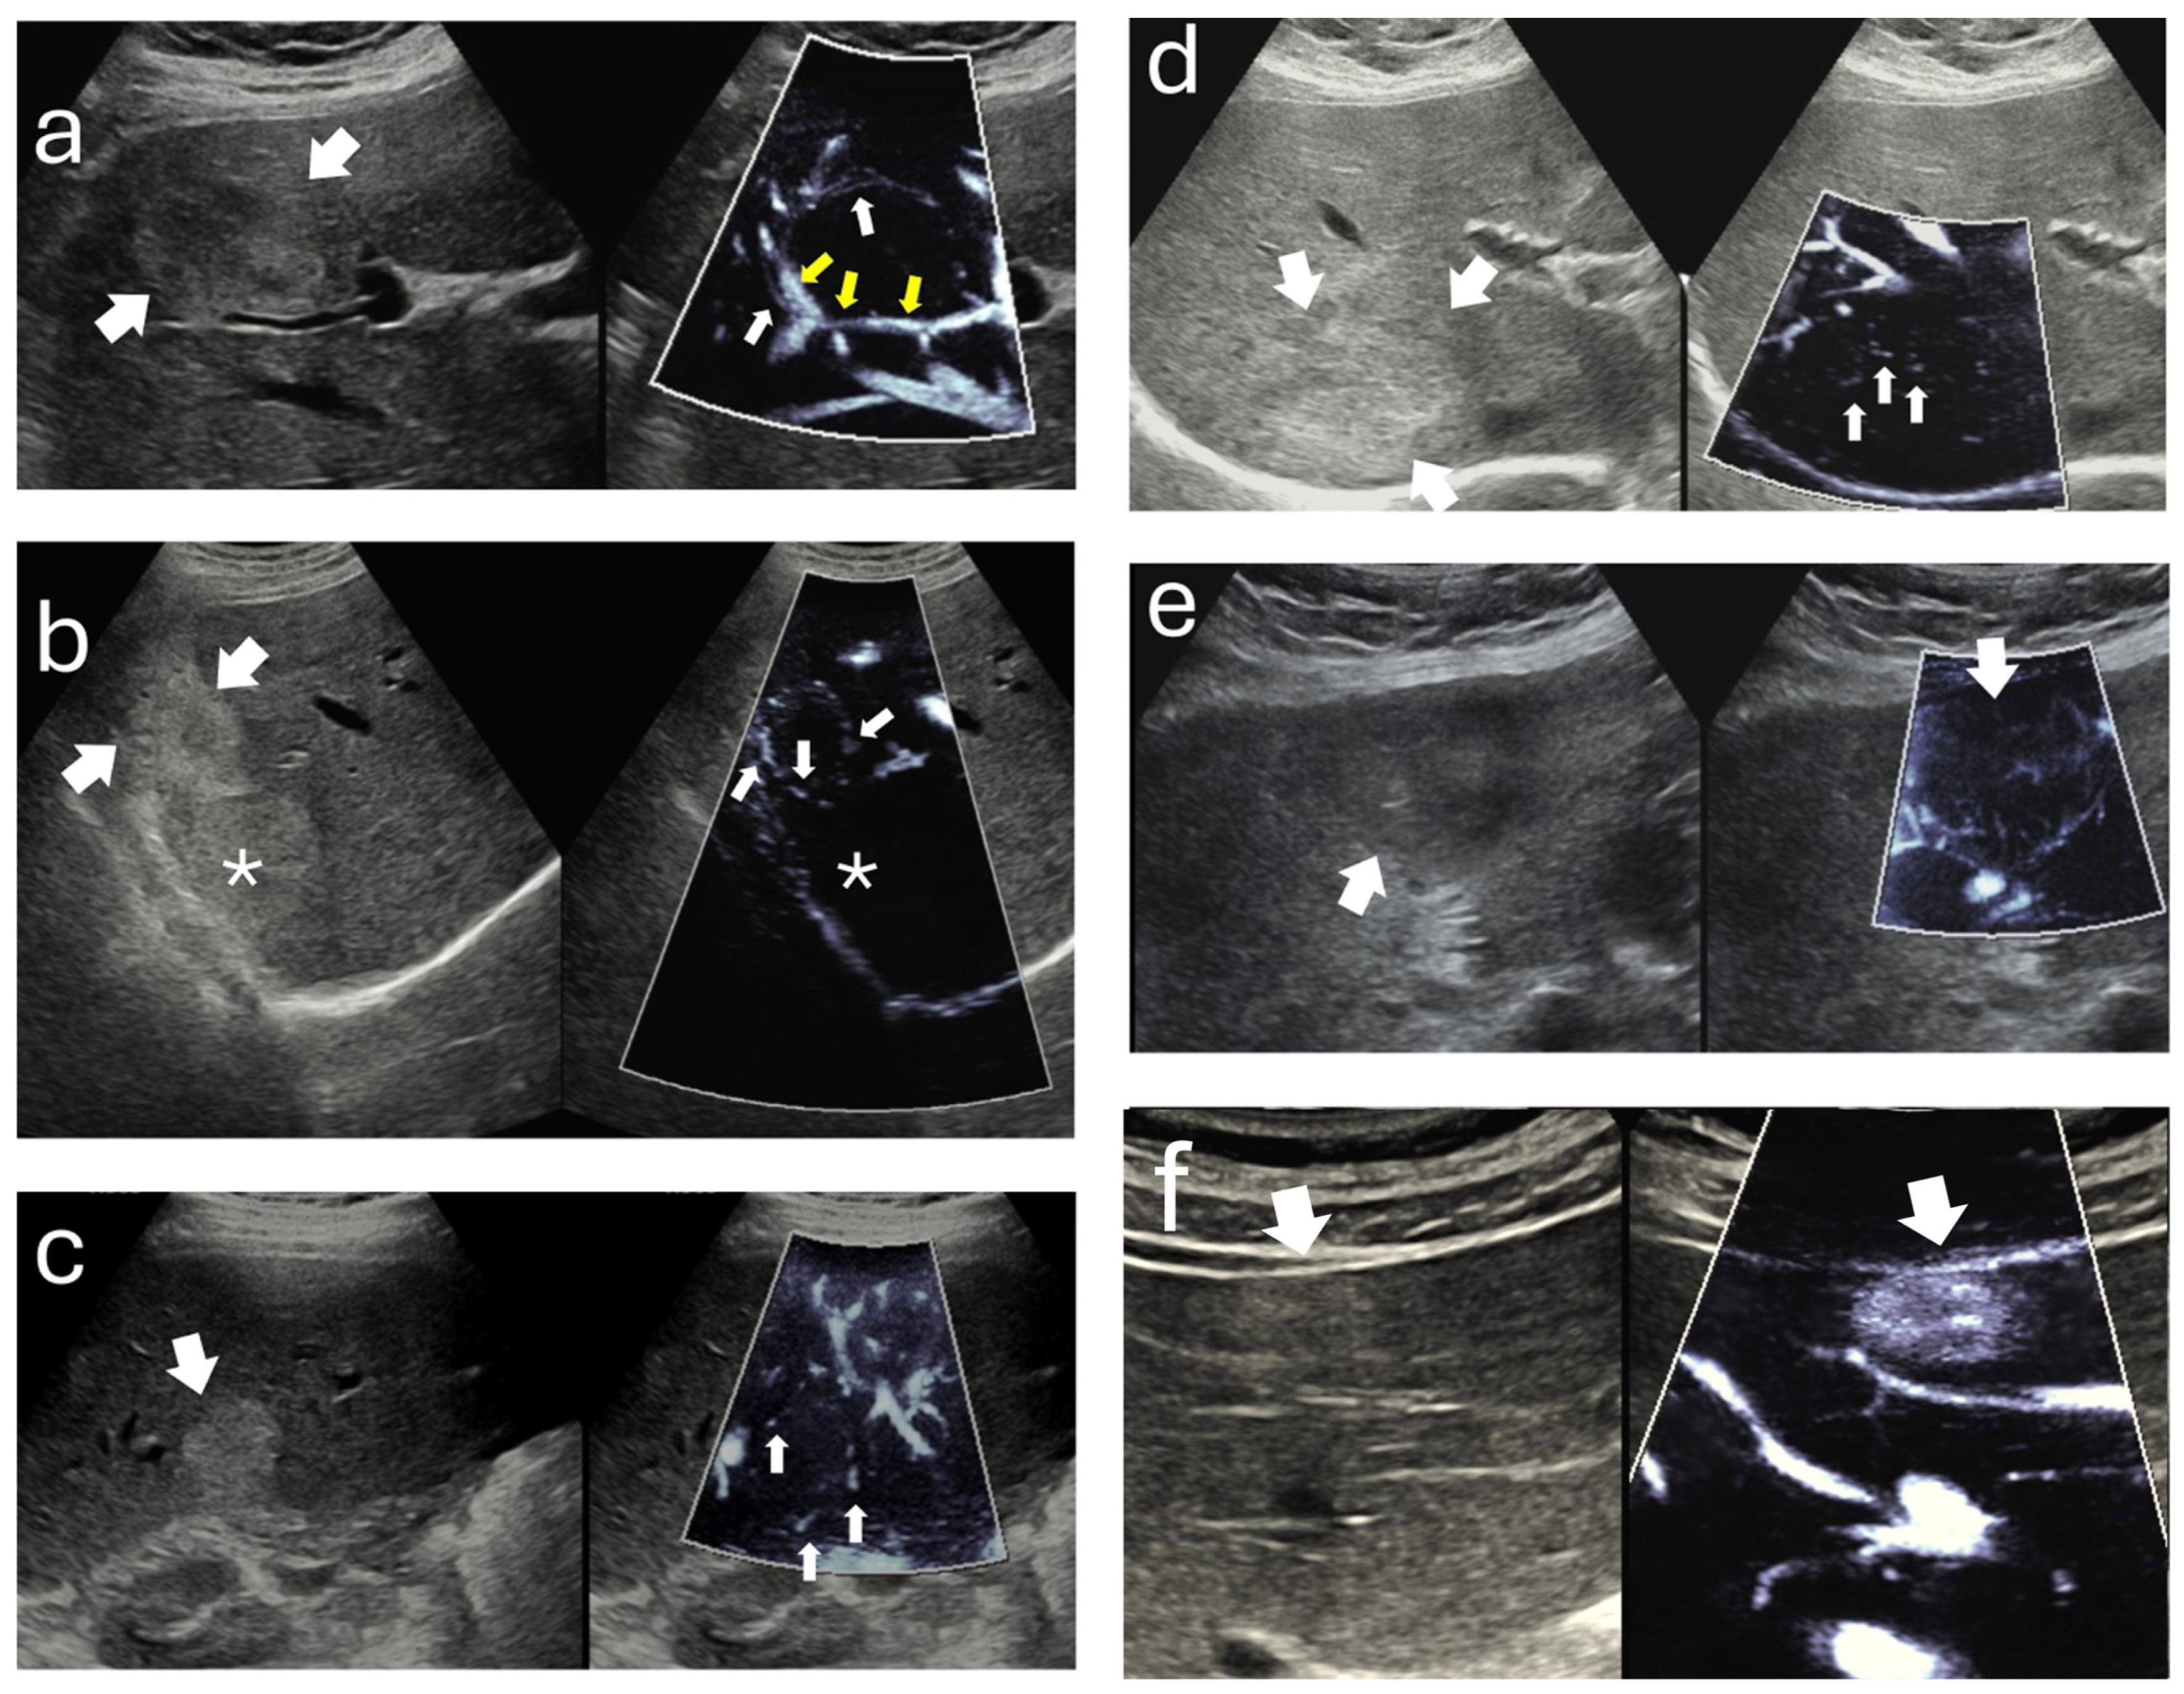

| Panel B. Doppler/MI outcomes and MI signal distribution (appearance categories) | |

| CDI/PDI flow present—n (%) | 0 (0.0) |

| MI signal present—n (%) | 68 (94.4) |

| MI signal absent—n (%) | 4 (5.6) |

| Depth by MI signal (mm), median (IQR) | No MI signal: 85 (65.5–102) vs. MI-positive: 41.5 (27.5–59); p < 0.05 |

| MI patterns (calculated within MI-positive lesions, n = 68) | |

| Non-specific—n (%) | 17 (25.0) |

| Nodular-rim—n (%) | 15 (22.1) |

| Strip-rim—n (%) | 12 (17.6) |

| Central dot-like—n (%) | 11 (16.2) |

| Peripheral dot-like—n (%) | 7 (10.3) |

| Staining—n (%) | 6 (8.8) |

| Inter-observer agreement | κ = 0.821 (95% CI, 0.767–0.921) |